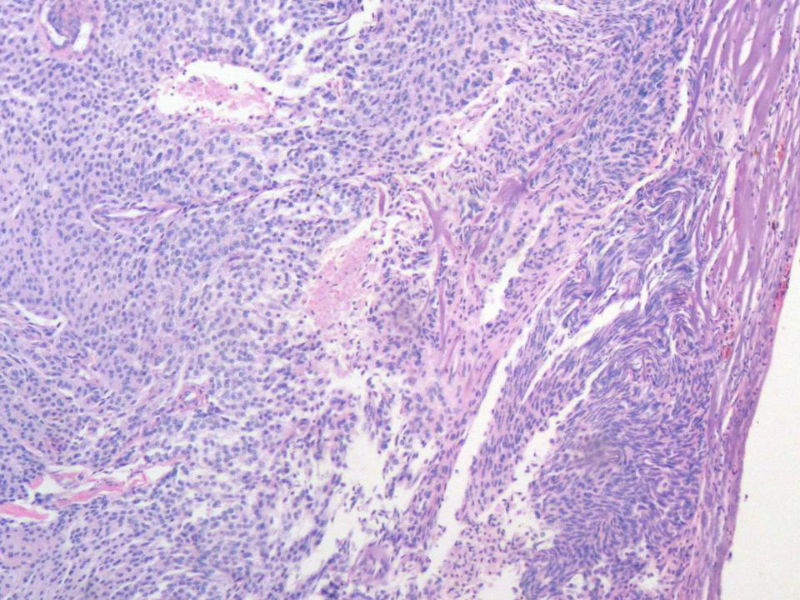

女,64岁,头晕半月,CT检查颅内左颞叶占位,侵犯颅骨和颞肌,手术切除肿物。肉眼,灰白色结节状肿物,3X3X2厘米,边界不清,切面灰黄色,质软。

特别提示:手术前曾做过介入肿瘤栓塞。镜下核分裂15/HP。脑左颞部占位图1

恶性脑膜瘤,有肌肉和骨的侵犯。

梭形细胞与上皮样漩涡状结构,富于细胞,见个别沙砾体,并见肿瘤性坏死。颅骨及其横纹肌等软组织内见肿瘤呈侵袭性生长。但细胞异型性不是很大。鉴别:

1)恶性脑膜瘤

2)非典型性脑膜瘤

由于非典型性脑膜瘤也可以发生地图状坏死,甚至侵袭性生长。需要计数核分裂数/10HPF,以资鉴别诊断。